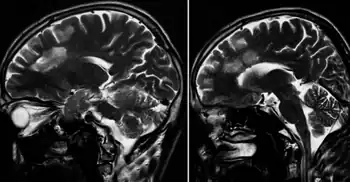

Lesions under MRI are distinctive due to their natural concentric shape.

Lesions under MRI

The features of the MRI and the characteristics of the lesion can be correlated when a biopsy has been taken, providing a way to standardize the future MRI diagnosis[24]

Baló's concentric sclerosis lesions can be distinguished from normal lesions on MRI showing alternating hypointense and hyperintense layers[25]

Baló's concentric lesions can be viewed using the myelin water imaging techniques. This is a special MRI sequence that shows the myelin's percentage of water content.[26]

Pattern III lesions, including Baló lesions, have a specific initiation pattern under MRI (MRILIP) consisting in showing Gadolinium enhancement before FLAIR MRI appearance.[27]

Under 7-Tesla MRI Ball lesions show a center vein, like in MS.[28]